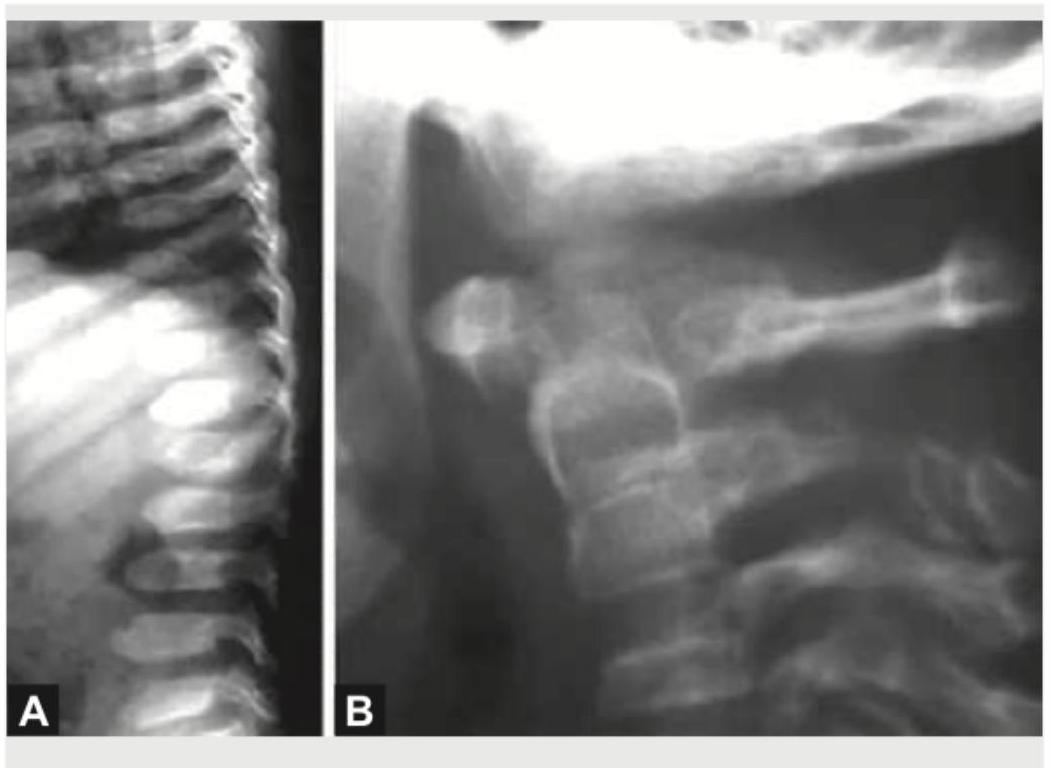

Comment on the diagnosis based on X-ray spine findings:

Explanation: **_Mucopolysaccharidosis_** - The imaging features, particularly the **beaked vertebrae** and **widespread bone changes** (dysostosis multiplex), are characteristic of mucopolysaccharidosis. - The vertebral bodies show **anterior inferior beaking**, especially in the lumbar spine, which is a hallmark finding. - This is a storage disorder affecting glycosaminoglycan metabolism, leading to skeletal dysplasia. *Osteopetrosis* - Osteopetrosis is characterized by **increased bone density** ("marble bones") due to defective osteoclast function. - The X-ray does not show diffusely increased bone density; instead, it demonstrates abnormal vertebral shape with anterior beaking. *Spondylolisthesis* - Spondylolisthesis involves the **forward displacement of one vertebra over another**, typically due to a defect in the pars interarticularis or degenerative changes. - This condition presents with vertebral slippage, which is not evident in the provided X-rays. *Sickle cell anaemia* - Sickle cell anaemia can cause bony changes such as **H-shaped vertebrae** due to bone infarcts and avascular necrosis. - The appearance of the vertebrae with anterior beaking is not typical for sickle cell disease.